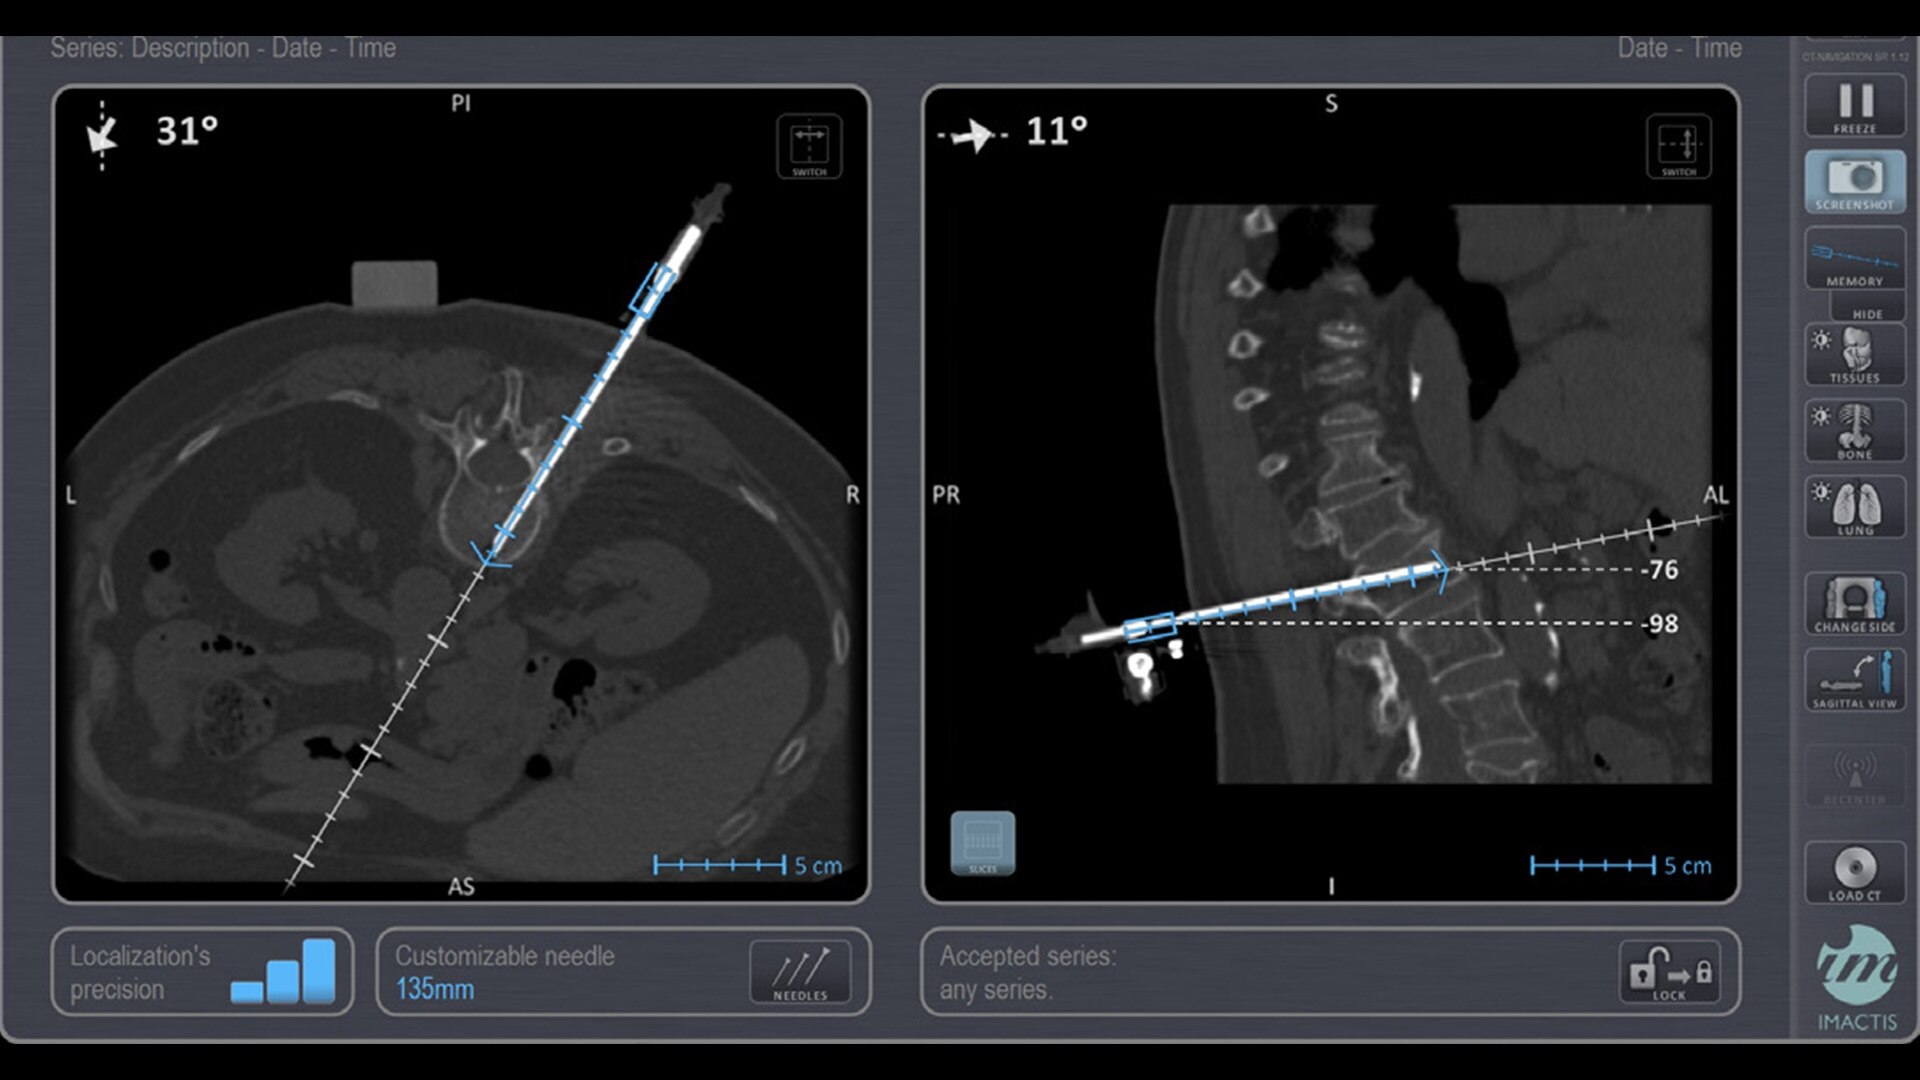

In interventional radiology, the success of the percutaneous procedure depends on correct needle positioning. The Imactis system helps the radiologist place one or more needles with great accuracy, in less time and with fewer control scans.

With real-time image reconstruction, live interactive navigation and no limit in angulation, the optimal clinical choices are clear.

Live 3D needle tracking, precise reproduction of your planned trajectory and continuous needle depth measurement help ensure optimal needle placement.